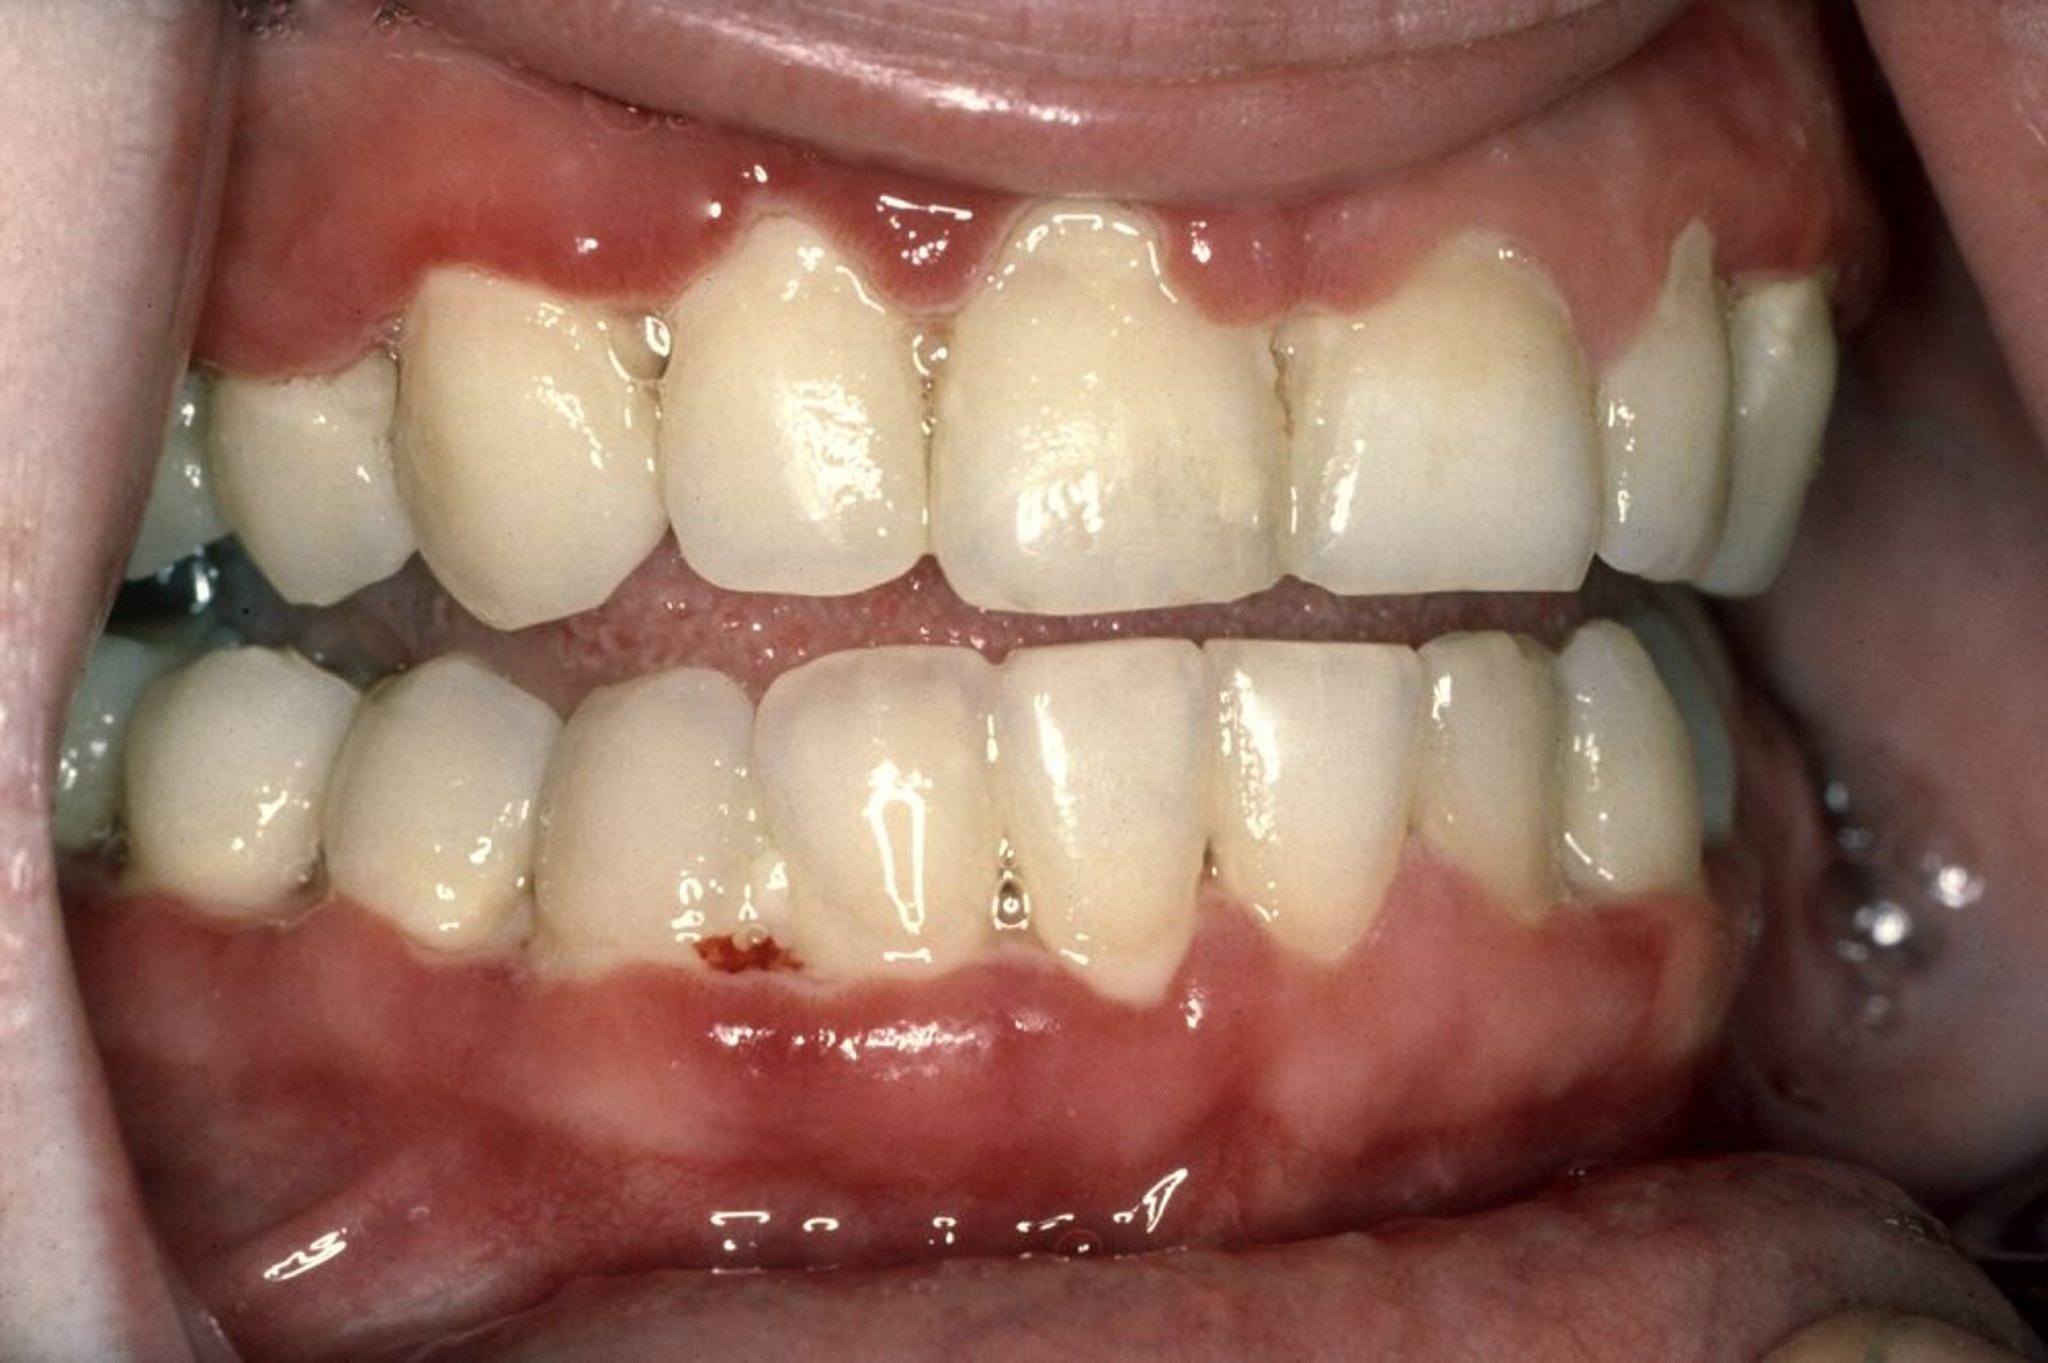

Gingivite ulcéro-nécrosante aiguë

La gingivite ulcéro-nécrosante aiguë (GUNA) se caractérise par des gencives douloureuses qui saignent facilement, l’érosion et la nécrose du tissu gingival interdentaire, et une haleine fétide. Sur cette photo, le tissu gingival est très rouge. Mieux visualisée le long de la ligne gingivale avant inférieure, on observe également une fine ligne de tissu gris et nécrosé (pseudomembrane) qui saigne facilement.

Photo publiée avec l’aimable permission de Craig Fowler, DDS